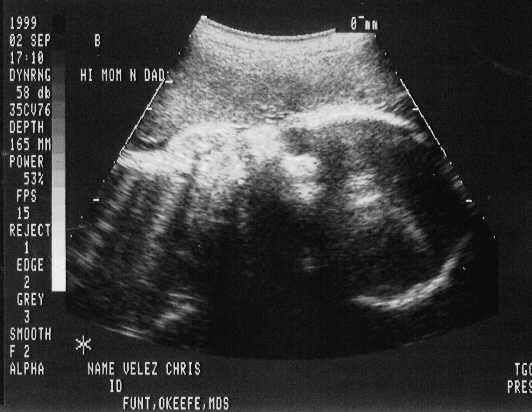

September 02, 1999 Sonograms

Kris is in her 33rd week. She can go in labor in 3 weeks!

Kristofer weighs 4.4 pounds.

The doctor says he can't believe how close they are in weight. They are almost NEVER this close in size.

Kristofer Henry

sono-0902-b1.JPG - 22.9 K